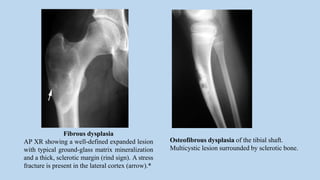

Fibrous dysplasia

AP XR showing a well-defined expanded lesion

with typical ground-glass matrix mineralization

and a thick, sclerotic margin (rind sign). A stress

fracture is present in the lateral cortex (arrow).*

Osteofibrous dysplasia of the tibial shaft.

Multicystic lesion surrounded by sclerotic bone.